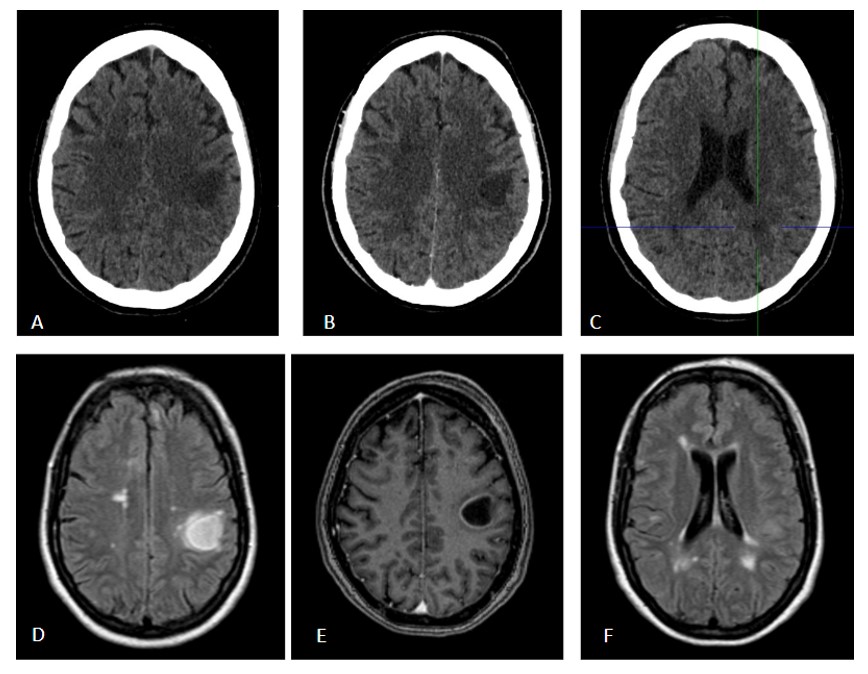

(A y C) Cortes axiales de TC de cráneo sin contraste (B) Corte axial de TC de cráneo con contraste en fase parenquimatosa. Identificamos una lesión focal intraparenquimatosa parietal izquierda, hipodensa, de bordes mal definidos, con leve efecto de masa sobre los surcos de la convexidad, de aproximadamente 23 x 27 mm (AP x T). Tras la administración de contraste (B) presenta un tenue realce lineal de contraste periférico, en forma de anillo incompleto, siendo más marcado en la vertiente más interna de la lesión. (C) Se objetivan en la sustancia blanca supratentorial otras imágenes pseudonodulares, hipodensas y menor tamaño, con ausencia de captación de CIV.

(D y F) RM de cráneo, secuencias axiales FLAIR pre-contraste. Se visualizan múltiples lesiones hiperintensas en FLAIR y en resto de secuencias con TR largo (no mostradas), con distribución predominantemente periventricular y yuxtacortical (más de 30 lesiones supratentoriales), la de mayor tamaño de aspecto nodular en sustancia blanca yuxtacortical- subcortical de región postcentral izquierda, con hiperseñal central en FLAIR y fino anillo periférico hipointenso, muestra un pequeño halo de edema perilesional vasogénico. (E) RM de cráneo, secuencia axial T1 tras administración de contraste; la lesión focal postcentral izquierda, muestra un realce periférico, «en anillo incompleto», con predominio del realce en su vertiente más medial, lo que sugiere actividad inflamatoria activa. Hallazgos sugestivos de lesión tumefactiva de tipo desmielinizante, el resto de lesiones no muestran captación de contraste.

DIAGNÓSTICO: LESIÓN TUMEFACTIVA DESMIELINIZANTE.